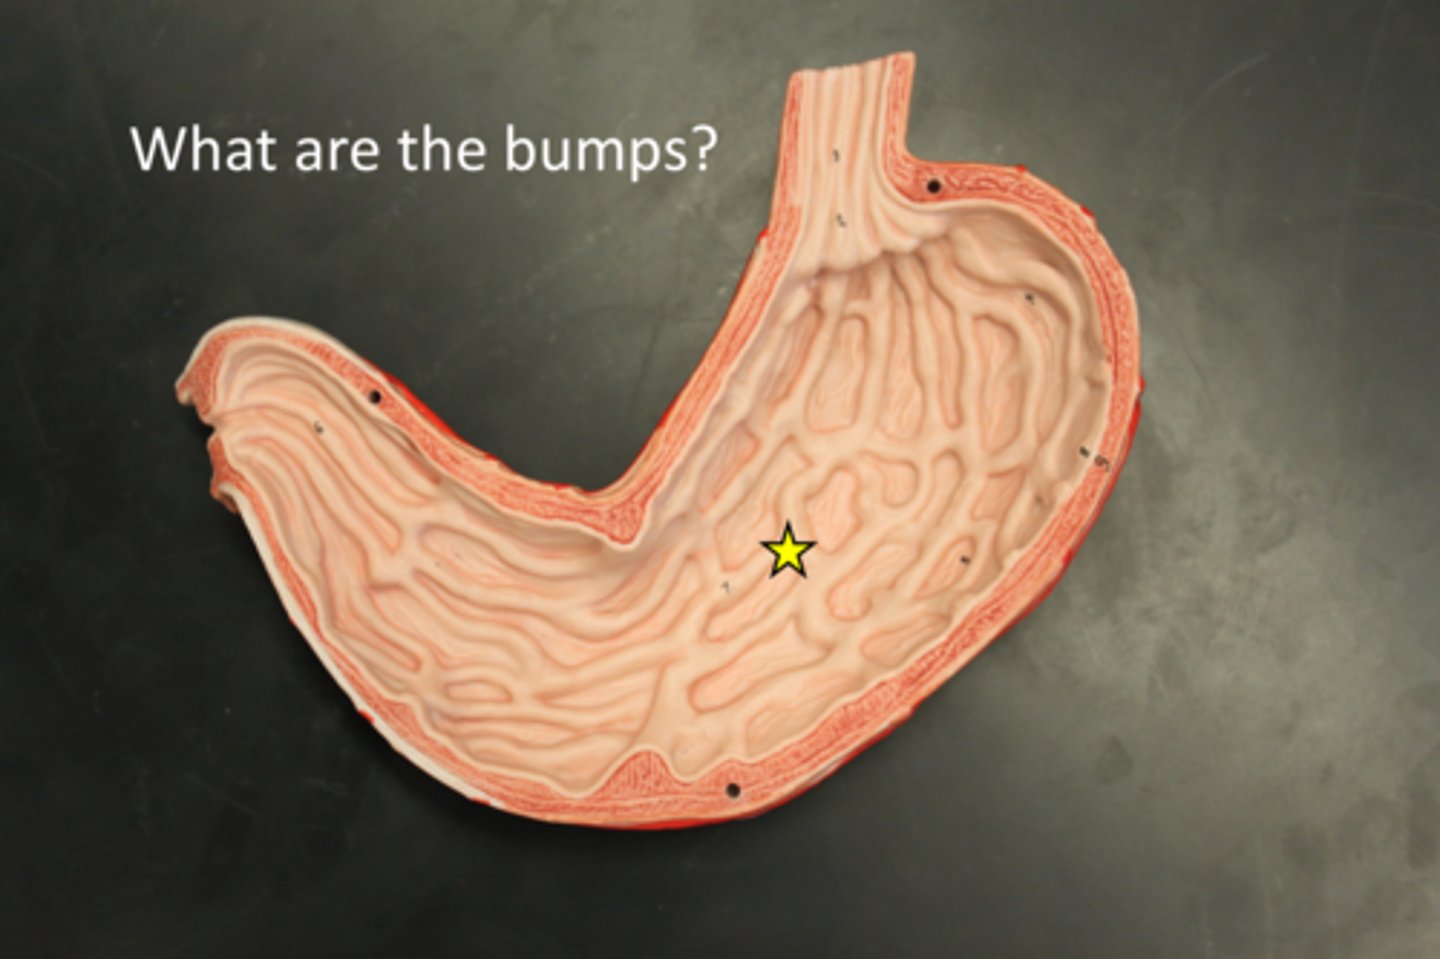

rugae